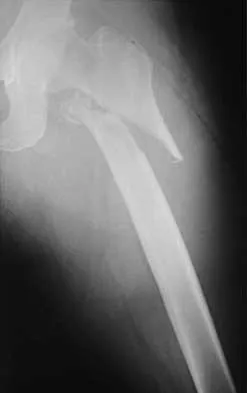

Figure 38a shows the radiograph of a 12-year-old boy who underwent a reamed intramedullary nailing for a closed femoral shaft fracture. One year after rod removal, he reports groin pain. A current radiograph is shown in Figure 38b. The findings are most likely the result of

Explanation

Osteonecrosis of the femoral head is a known complication from the use of rigid intramedullary nails for femoral fractures in adolescents. When the nails are placed through the piriformis fossa, the lateral ascending vessels of the femoral neck may be injured, resulting in osteonecrosis of the femoral head in 1% to 2% of patients. Rigid reamed nails placed into the piriformis fossa are contraindicated in children with open growth plates because the physis is a barrier to blood supply and the ligamentum teres does not provide sufficient vascularity. Alternative fixation methods for femoral fractures in adolescents include external fixation and open reduction and internal fixation. Nailing through the tip of the trochanter may decrease the incidence of this serious complication. Letts M, Jarvis J, Lawton L, et al: Complications of rigid intramedullary rodding of femoral shaft fractures in children. J Trauma 2002;52:504-516. Stans AA, Morrissy RT, Renwick SE: Femoral shaft fracture treatment in patients age 6 to 16 years. J Pediatr Orthop 1999;19:222-228. Buckley SL: Current trends in the treatment of femoral shaft fractures in children and adolescents. Clin Orthop 1997;338:60-73.